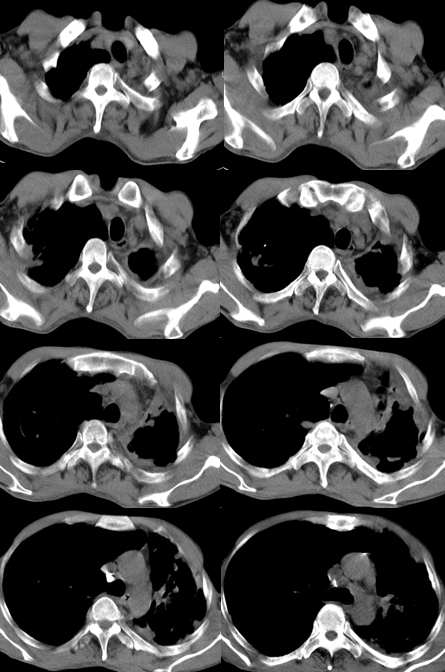

男,58岁,胸痛、咳嗽一周,无痰血;否认其他特殊病史

两侧胸廓不对称,左侧明显变小,两肺上叶可见空洞,纤维条索影,两肺下叶多发斑片状影。考虑两肺上叶继发性肺结核伴两肺下叶支气管播散。

影像;两上肺及左中下肺多个大小不一薄壁不规则空洞,部分空洞可见少量液平,周围拌有条索影,纵隔,心脏左移,两中下肺多发散在小结节以及小囊状阴影。

根据病变的部位、形态及密度改变符合慢性纤维空洞型肺结核,不同时期的病灶均有。

符合陈旧性慢纤空型肺tb,左侧上肺片状影考虑tb复发;

左侧慢性纤维空洞型肺结核,双下肺播散,左侧牵引性支扩